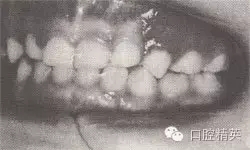

患者,男,4歲,乳牙。磨牙近中關(guān)系。前牙反頜,下頜前突,位置前移。

診斷:乳前牙反頜,安氏Ⅲ類,毛氏Ⅱ¹。

矯治設(shè)計(jì):上頜頜墊式活動(dòng)矯治器。下頜后退位解剖式頜墊,舌簧推乳上切牙向唇側(cè),調(diào)磨頜墊。

治療時(shí)間:1.5個(gè)月,乳前牙反頜解除,乳切牙達(dá)到正常覆頜、覆蓋。下頜回到正常位置。

圖8-37 安氏Ⅲ類錯(cuò)頜,乳前牙反頜矯治前后面頜像

矯治前面相

矯治前咬合圖

矯治后咬合圖